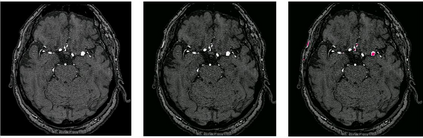

Time-of-Flight Magnetic Resonance Angiographs (TOF-MRAs) enable visualization and analysis of cerebral arteries. This analysis may indicate normal variation of the configuration of the cerebrovascular system or vessel abnormalities, such as aneurysms. A model would be useful to represent normal cerebrovascular structure and variabilities in a healthy population and to differentiate from abnormalities. Current anomaly detection using autoencoding convolutional neural networks usually use a voxelwise mean-error for optimization. We propose optimizing a variational-autoencoder (VAE) with structural similarity loss (SSIM) for TOF-MRA reconstruction. A patch-trained 2D fully-convolutional VAE was optimized for TOF-MRA reconstruction by comparing vessel segmentations of original and reconstructed MRAs. The method was trained and tested on two datasets: the IXI dataset, and a subset from the ADAM challenge. Both trained networks were tested on a dataset including subjects with aneurysms. We compared VAE optimization with L2-loss and SSIM-loss. Performance was evaluated between original and reconstructed MRAs using mean square error, mean-SSIM, peak-signal-to-noise-ratio and dice similarity index (DSI) of segmented vessels. The L2-optimized VAE outperforms SSIM, with improved reconstruction metrics and DSIs for both datasets. Optimization using SSIM performed best for visual image quality, but with discrepancy in quantitative reconstruction and vascular segmentation. The larger, more diverse IXI dataset had overall better performance. Reconstruction metrics, including SSIM, were lower for MRAs including aneurysms. A SSIM-optimized VAE improved the visual perceptive image quality of TOF-MRA reconstructions. A L2-optimized VAE performed best for TOF-MRA reconstruction, where the vascular segmentation is important. SSIM is a potential metric for anomaly detection of MRAs.